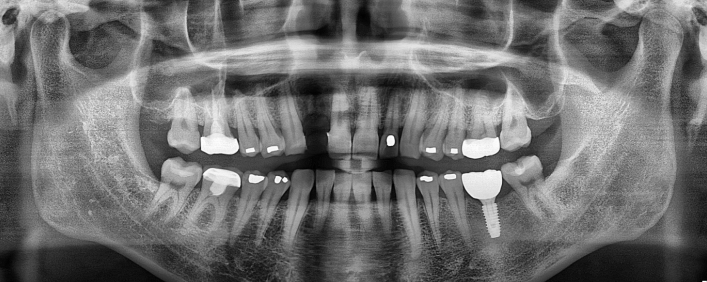

임플란트 재수술

임플란트 수술, 재실패는 없어야 합니다.

임플란트 실패에는 임플란트 주위염, 픽스처 문제, 보철물 문제 등 다양한 원인이 있습니다.

신경손상과 염증없이 안전한 재수술을 위해서는 첫 시술보다 더욱 섬세하고 전문적인 접근으로

정확한 정밀검사와 충분한 의료진 상담을 받은 후 내 치아에 적합한 방법으로 진행해야 합니다.

임플란트 치료사례

서울스마트치과는 결과로 증명합니다.

위 치료 사례는 서울스마트치과에서 직접 치료를 받고, 환자 본인의 동의를 얻어 게재된 사진으로 무단 인용, 도용, 재배포 시 민/형사상 책임을 질 수 있습니다.